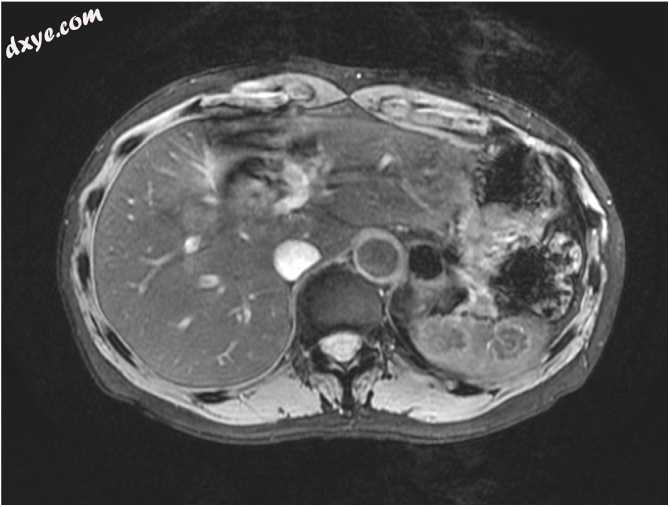

在常规健康检查期间,腹部超声检查发现一位59岁的女性因腹部异常结节被转诊到作者医院。她过去的病史包括7年前输卵管的脓肿和双侧卵巢。基线实验室检查,包括全血细胞计数,电解质(包括钙)的血清水平,肾和肝功能检查,可溶性白介素2受体(sIL-2R)水平以及肿瘤标志物癌胚抗原(CEA)和碳水化合物抗原的水平19-9(CA19-9)在正常范围内。腹部超声检查显示脾脏大小正常,并有三个小尺寸的低回声结节。腹部增强的计算机断层扫描(CT)和磁共振成像(MRI)证实了脾脏中存在多个病变。这三个脾结节在T2加权图像上显示低信号,异质性增强,直径分别为22、17和9mm(图1,图2)。在其他器官中未发现其他病变。

图 2

腹部的磁共振成像在T2加权图像上显示出低水平结节。

在本例中,腹部超声检查显示出大小不等的小回声结节,已通过CT证实,而MRI没有诊断优势。最初的诊断是良性肿瘤,例如纤维错构瘤或炎性假瘤。在随访4个月后,由于肿瘤大小的进展和PET-CT摄取18F-FDG的异常,进行了诊断性腹腔镜脾切除术。